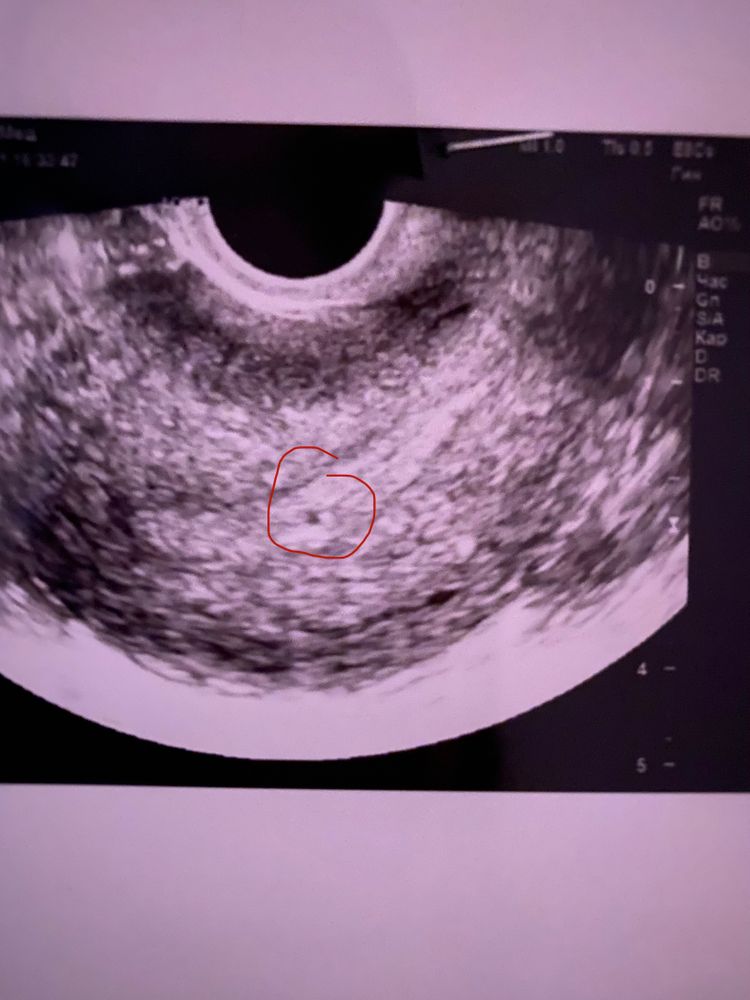

Оленька, вот якобы возможно эта пя,но опять же с точностью не сказали ,даже в заключении писать не стали Изображение

0

06.11.2021

Мама двоих (8 лет, 1 год) Нижний Новгород

Изображение Наталья Волгунова, вот моё, мне кажется очень похоже, только у вас может на пол миллиметра поменьше.

Наталья Волгунова, я конечно не врач, но при таком хгч я бы сказала что это ПЯ. Сходите на узи еще в другое место, где аппарат получше